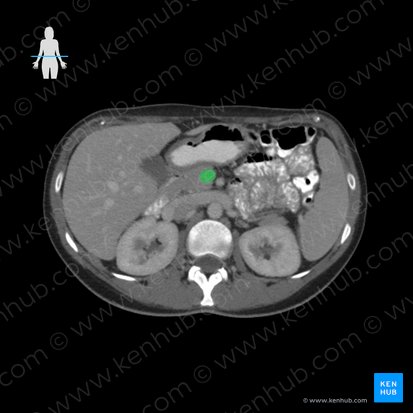

The superior mesenteric vein is a large abdominal vein that is formed by the small terminal veins that drain the ileum, caecum and vermiform appendix. It runs superomedially, traversing the mesentery of the small intestine. Along its course, the vein accompanies the superior mesenteric artery that runs on its left side.

The superior mesenteric vein terminates at the transpyloric plane (around the lower margin of the L1 vertebra) by merging with the splenic vein to form the hepatic portal vein.